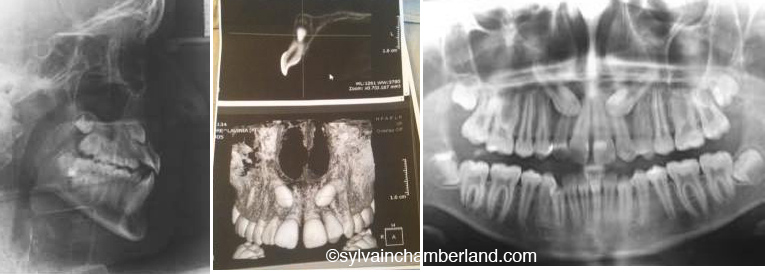

I introduce you to a case of a patient who comes to my office and who has 2 impacted canines that cause resorption of the incisors. Any traction attempt on the canines would have meant a more important damage to the incisors. The patient had a Class II malocclusion. I thus proposed a treatment including the removal of 2 permanent maxillary canines, but without any removal in the mandible. Notice that the treatment was initiated in the mandibular arch while waiting for the upper canines to be extracted. The treatment in the maxillary arch started in March a few weeks after the extraction surgery. Notice the resorption of teeth #21 and a little bit of teeth #22. Teeth #12 and #11 are less damaged.

The ceph show a class I relationshipm normal overjet and overbite. The 3D view shows the lateral incisors buccaly overlayed on the roots of the lateral incisors. The pan and the significant lack of space. I can see crowding of the lower right canine.

A CBCT will allow defining the position of the impacted canine relatively to the roots of the incisors more precisely.

A CBCT is a lot more serious to help in diagnosing an impacted canine and its relationship with nearby structures. To see examples where this imaging technique was a precious diagnostic help; follow this link

In your daughter’s case, it takes a cone beam computed tomography to determine the extent of the damages and the real position of the canines. In the above example, you can see the root resorption of the upper incisor and how close the crown of the canine is to the root of the incisors. It is another example where the therapeutic decision included the extraction of 3 premolars (#14, #34, #44) and the impacted canine (#23). With this being said, do not believe that I only do that, extract impacted canines. I show you exception cases, because the rule is rather to spare the canines.